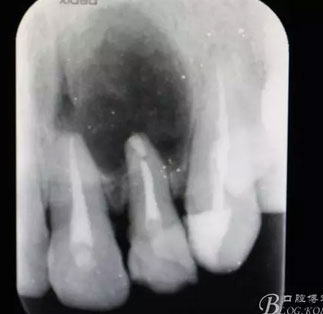

圖1.術(shù)前患者的x光根尖片檢查影像:22根尖完全位于囊腔內(nèi),牙槽骨吸收至嵴頂約5mm。22松動(dòng)Ⅰ度。

患者、相xx、男、38歲。主訴:左側(cè)上前牙牙床有一疙瘩半年余?,F(xiàn)病史:患者半年前無(wú)意識(shí)發(fā)現(xiàn)左側(cè)上牙床有一疙瘩,大小如花生米,無(wú)任何不適感覺(jué)。未做任何治療,最近感覺(jué)疙瘩增大,遂來(lái)我院就診。專(zhuān)科檢查:21、22牙冠顏色正常,叩診(-)。唇側(cè)前庭溝有一隆起,捫診有乒乓感,壓痛不明顯、x根尖片檢查:21、22根尖區(qū)橢圓形陰影。邊界清楚。診斷:22為中心的根尖囊腫。治療計(jì)劃:(1)21、22行根管治療術(shù)。(2)行21、22根尖囊腫摘除術(shù)+根管倒充填。患者同意治療方案,簽知情同意書(shū)。